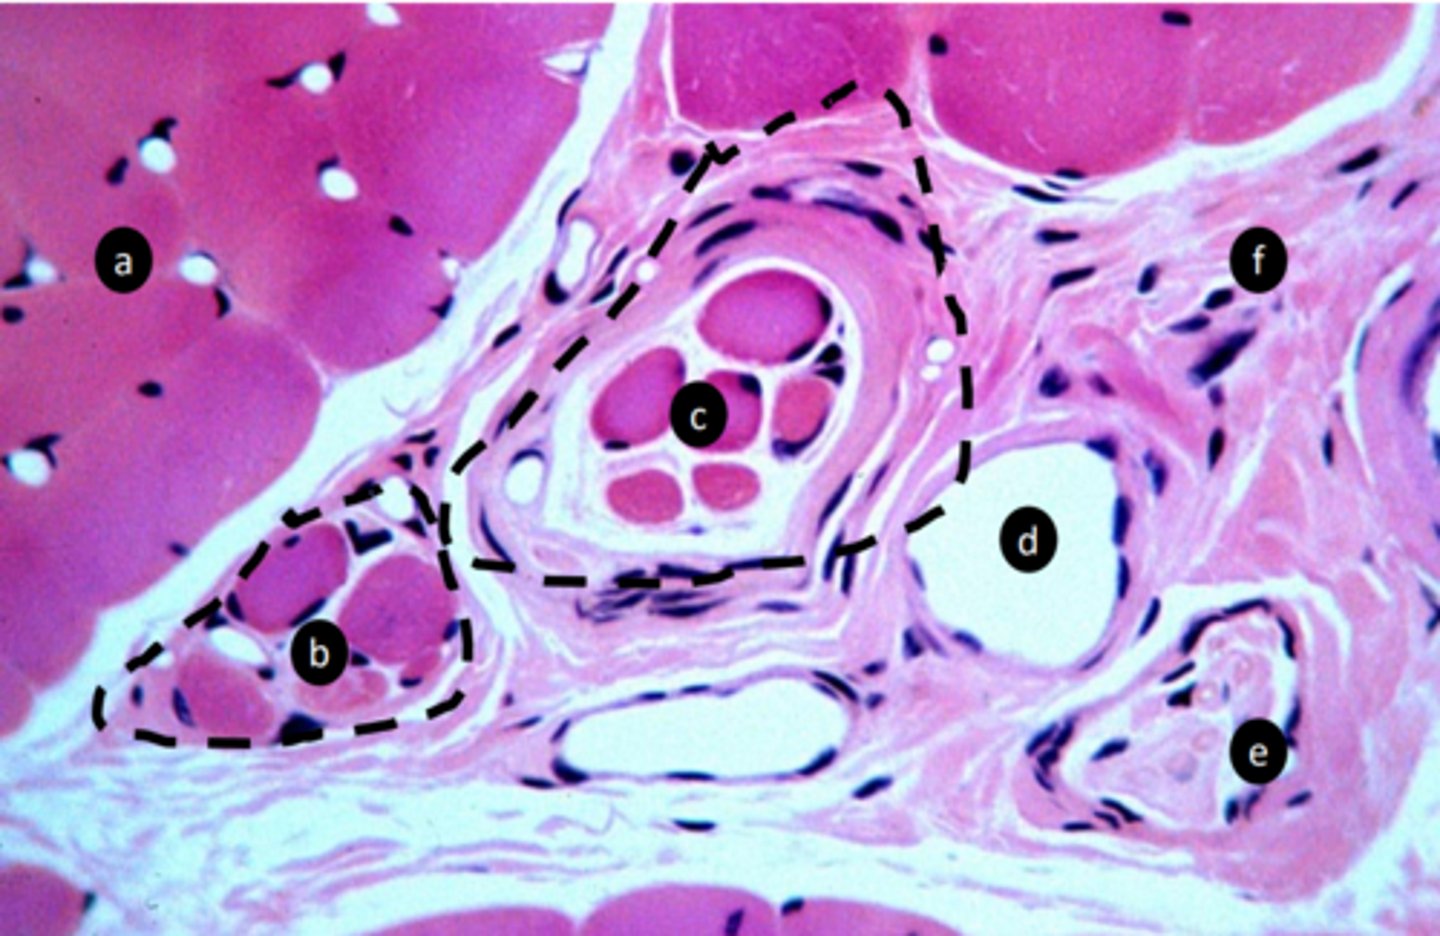

1

New cards

extrafusal myofibers

a: specific tissue type

<p>a: specific tissue type</p>

2

intrafusal muscle fiber

b: specific tissue type

<p>b: specific tissue type</p>

3

intrafusal muscle fiber (muscle spindle)

c: specific tissue type

<p>c: specific tissue type</p>

4

stretch receptor, proprioception: detect length and velocity

function of c?

<p>function of c?</p>

5

vein

e: structure

<p>e: structure</p>

6

nerve fibers

f: structure

<p>f: structure</p>